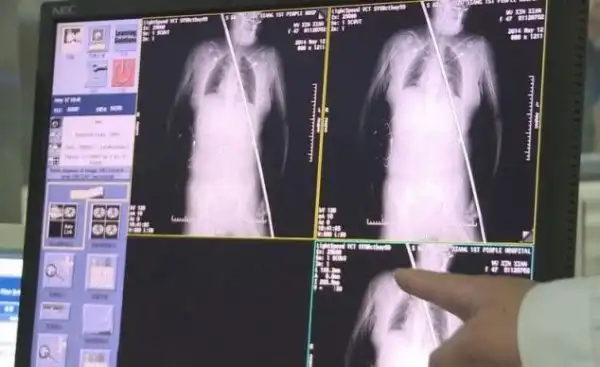

42-летняя Ву Синьсян работала на стройке в округе Дучань, провинция Цзянси. Под ней сломалась деревянная доска и она упала с высоты 6 метров на стальной прут, который пронзил ее насквозсь - от бедра до шеи через желудок.

Команда врачей в результате пятичасовой операции успешно извлекла двухметровый кусок арматуры. Если не возникнет заражение, то женщина полностью восстановится.